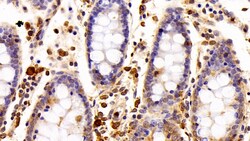

Ionized calcium-binding adapter molecule 1 (IBA1), also known by its gene name AIF1, is a protein expressed predominantly by microglia in the brain and spinal cord. This protein belongs to the EF-hand calcium-binding protein family and plays a crucial role in microglial activation and migration in response to brain injury or neuroinflammation. IBA1's function is integral to microglial motility and phagocytic activity, facilitating the cellular response to pathogenic stimuli and promoting tissue homeostasis and repair in the central nervous system. IBA1 serves as a reliable marker for activated microglia in various neurological disorders, including Alzheimer's disease, Parkinson's disease, and multiple sclerosis, where increased expression correlates with disease progression and severity. The protein's structural features enable it to bind calcium ions, inducing conformational changes that activate signaling pathways essential for microglial function. Its expression is highly regulated by inflammatory cytokines, underpinning its role in neuroimmune responses. Due to its specific expression in microglia during pathological conditions, IBA1 is widely used in research as a marker to study microglial status and activity, and it remains a focal point for understanding microglial involvement in neurodegenerative diseases.Specifications

| Immunohistochemistry (Paraffin), Western Blot | |